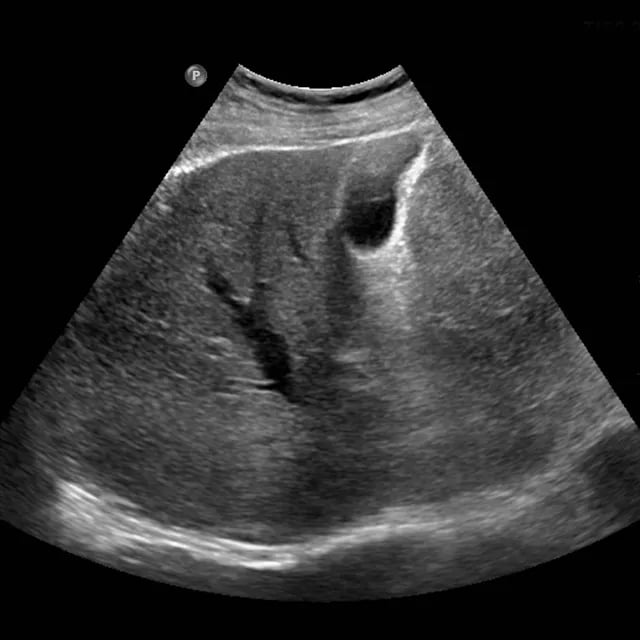

L’ecografia addominale rappresenta uno degli esami diagnostici per immagini più utilizzati e apprezzati in medicina, grazie alla sua non invasività, all’assenza di radiazioni ionizzanti e alla capacità di fornire informazioni in tempo reale sullo stato di salute degli organi interni.

L’ecografia addominale (spesso denominata “addome completo”) permette di visualizzare e valutare in dettaglio numerosi organi e strutture situate nella cavità addominale. Tra i principali elementi esaminati troviamo:

• Fegato: dimensioni, struttura, presenza di steatosi (fegato grasso), noduli, cisti o segni di infiammazione/cirrosi

• Cistifellea (colecisti) e vie biliari: ricerca di calcoli, infiammazioni (colecistiti), dilatazioni o ostruzioni

• Pancreas: valutazione di forma, dimensioni, presenza di masse, cisti o pancreatiti

• Milza: volume, omogeneità, eventuale ingrossamento

• Reni: forma, dimensioni, posizione, presenza di calcoli, cisti, idronefrosi o alterazioni parenchimali

• Vasi addominali maggiori (come l’aorta addominale): ricerca di aneurismi, trombosi o alterazioni di flusso

• Vescica (e vie urinarie): volume, pareti, residuo post-minzionale, calcoli o lesioni

• Organi pelvici (a seconda del sesso e del quesito clinico): utero e ovaie nella donna, prostata e vescichette seminali nell’uomo

L’esame consente inoltre di individuare masse anomale (cisti, tumori benigni o maligni), linfonodi ingrossati, liquido libero in addome o altre alterazioni che possono spiegare sintomi come dolore addominale, alterazioni degli esami del sangue, febbre di origine sconosciuta o controllo di patologie note.